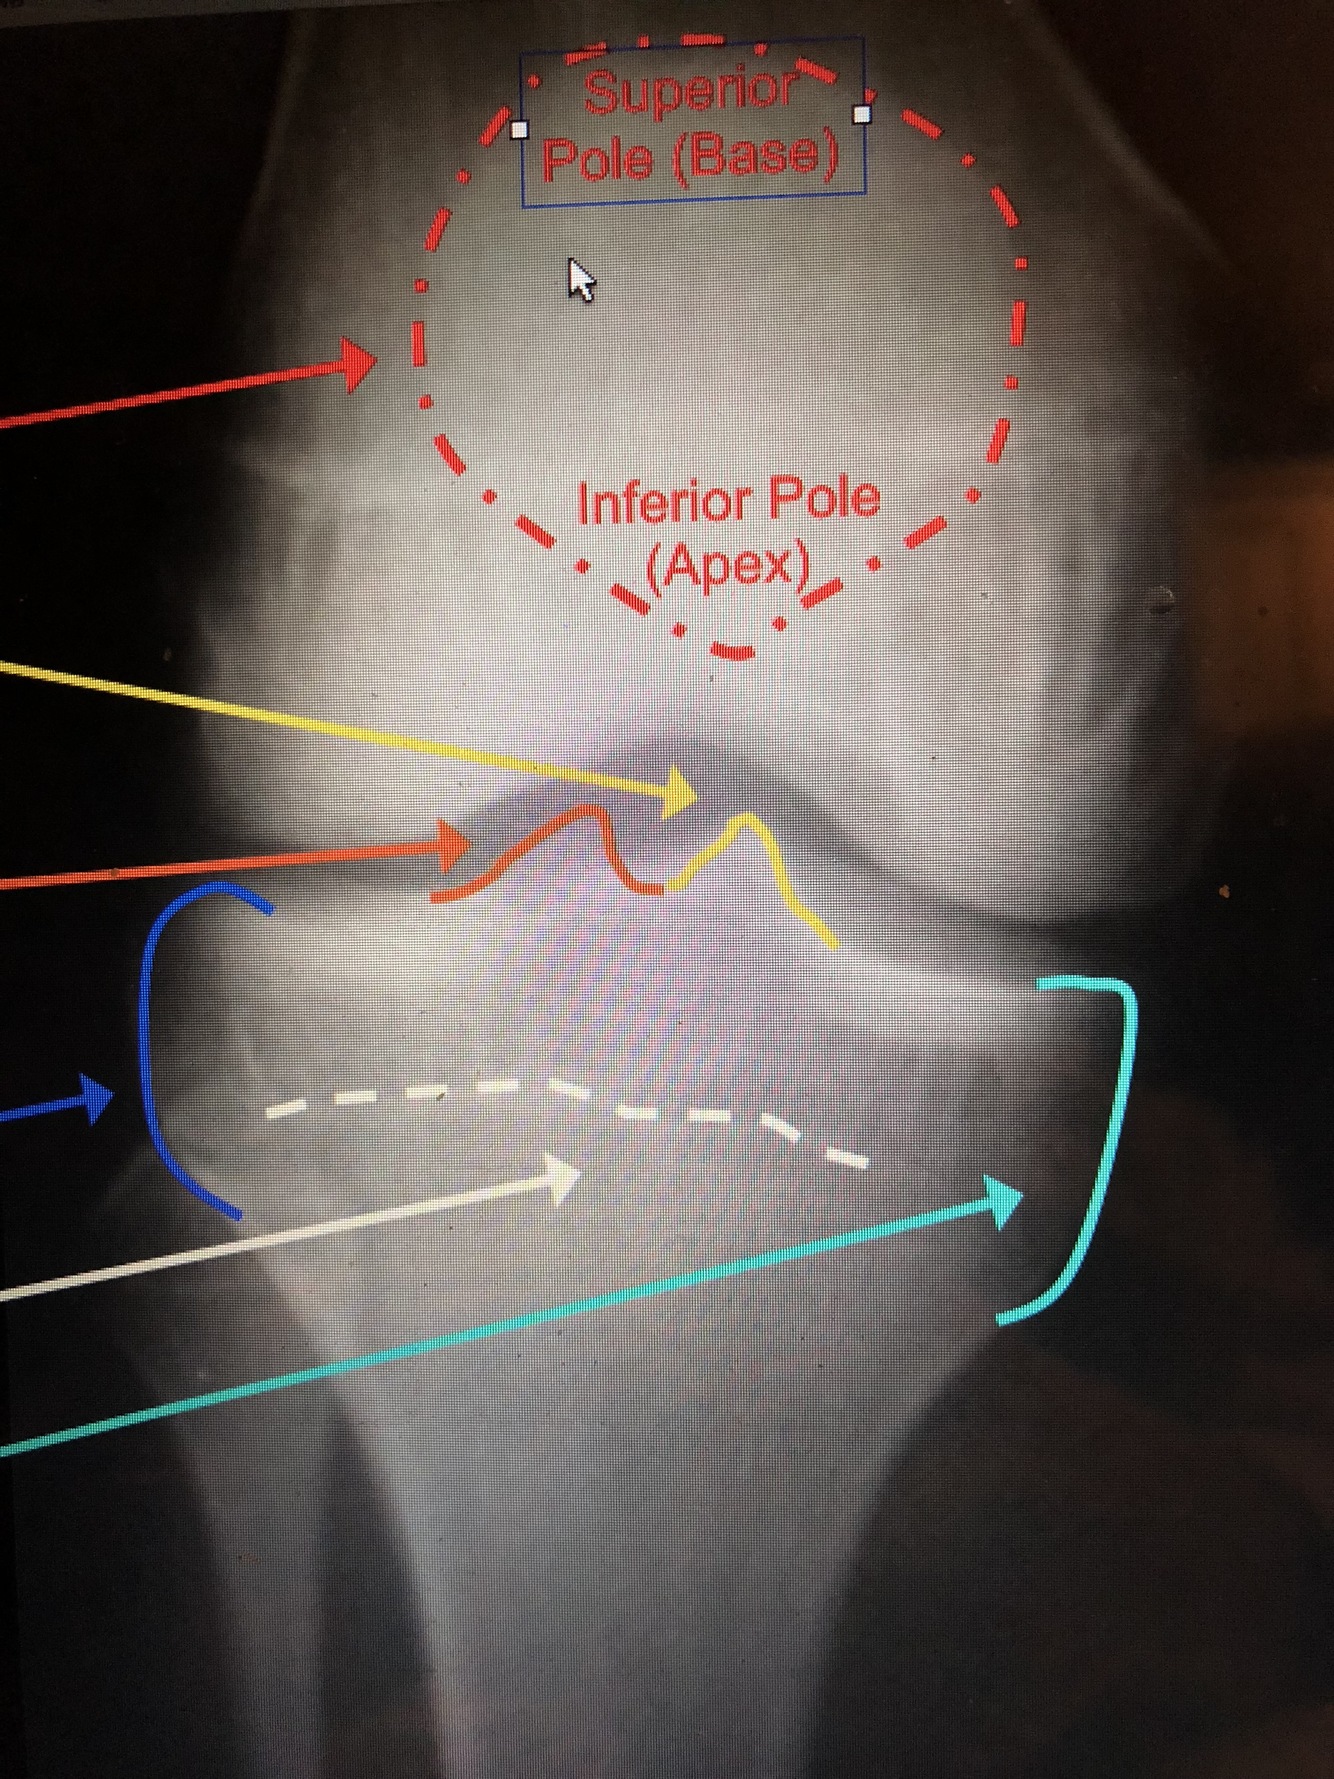

What is the dark blue line?

Superior Pole (Base) of the Patella

Inferior Pole (Apex) of the Patella

What is the solid white line?

Dorsal / posterior ridge